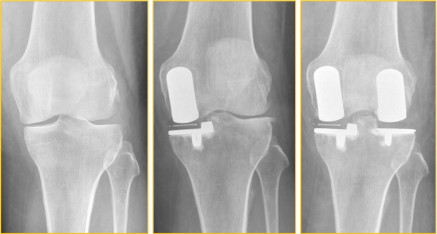

Behandlung einer Knie-Arthrose mit 2 Schlittenporothesen

Wir zeigen die Bilder einer Patientin, bei der sich nach der erfolgreichen Behandlung einer innenseitigen Knie-Arthrose mittels innenseitiger Schlittenprothese Schmerzen und Verschleißzeichen auf der Knie-Außenseite entwickelt haben. Die Behandlung erfolgte jetzt mittels einer außenseitigen Schlittenprothese. So können weiterhin alle Kniegelenksbänder und der normale Bewegungsablauf des Kniegelenks erhalten werden. Zusätzlich, und das ist für jeden Patienten von enormer Bedeutung, ist die Rehabilitation nach einer ein- oder beidseitigen Schlittenprothese viel kürzer als bei einer Komplettprothese.